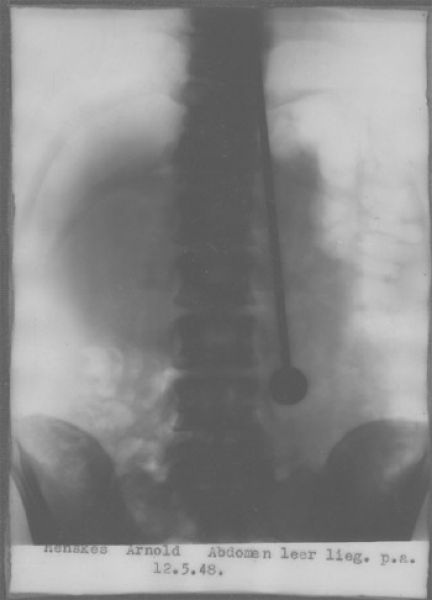

Конечно, Дажо проверяли врачи, причем не раз. В конце мая 1947 года он продемонстрировал свои таланты в Цюрихском кантональном госпитале. Как обычно, Мирин разделся до талии. Когда ассистент пронзил рапирой сердце, легкие и почки, он, как обычно, не почувствовал боли и не проронил ни капли крови.

Чтобы исключить возможность гипноза, было решено сделать рентген, но медики не знали, как доставить его до рентгеновского кабинета — ведь носилки не приспособлены к транспортировке людей, пронзенных рапирами.

Дажо успокоил их, сказав, что сам дойдет куда нужно — с рапирой, естественно. Снимки исключили всякие сомнения: клинок прошел через несколько жизненно важных органов, но не причинил никаких повреждений.